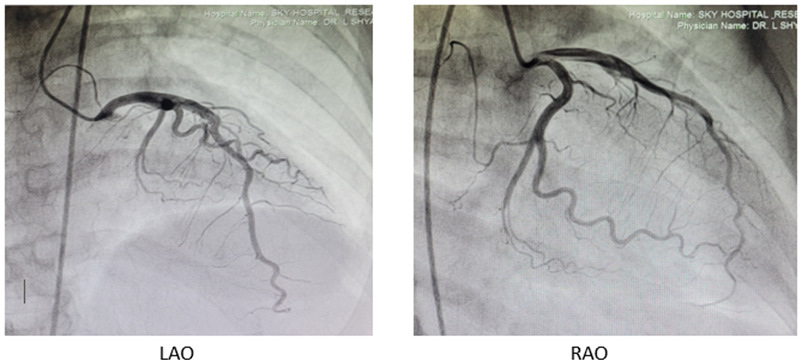

Post-Thrombolytic therapy coronary angiogram revealed fully recanalised the LAD Figure:3(c). Patient’s condition improved. She was mobilized and stable at the time of discharge on April 18, 2024.

Figure:3(c): Case 3 patient’s CAG photos showing fully recanalised LAD.